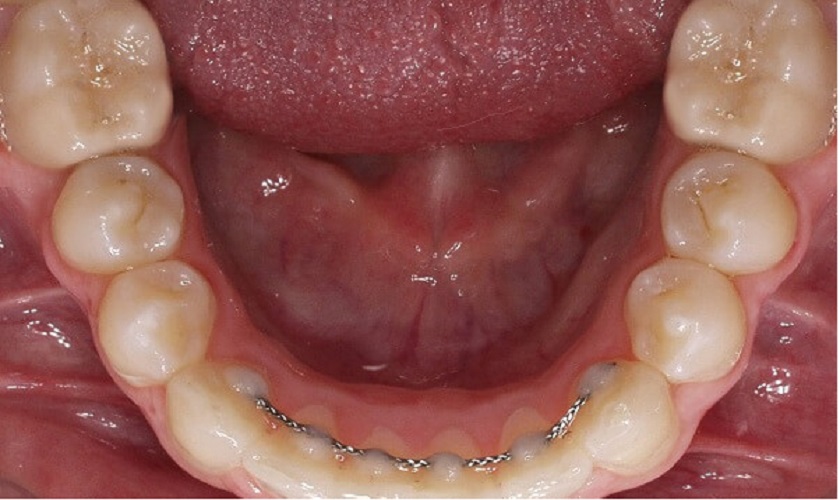

Khi răng không có bệnh lý, vẫn khỏe mạnh và bị lung lay do va đập hoặc các tác động ngoại lực khác, bác sĩ sẽ nẹp cố định răng của bạn bằng dụng cụ chuyên dụng. Sau một thời gian, răng bạn sẽ dần ổn định lại và quay về trạng thái ban đầu.

Nẹp cố định răng trong trường hợp lung lay răng do va đập mạnh